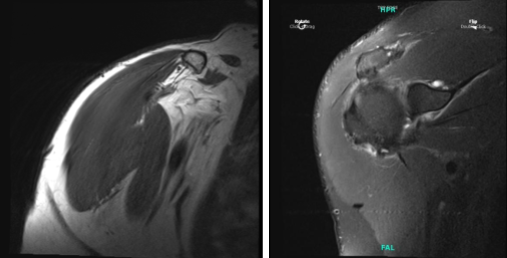

After a week, the patient presented his MRI. Impression as follows: Mild-moderate supraspinatus and infraspinatus tendinosis, with mild bursal fraying of junctional-zone fibers. Small, low-grade interstitial tear within the inferior subscapularis tendon.

Background mild-moderate subscapularis tendinosis, with low-grade intrasubstance fissuring superiorly. Complete versus near-complete rupture of the intra-articular segment of the biceps tendon, with retraction of the distal tendon stumps of the bicipital groove. Additional shortness and segment split tearing the extra-articular biceps tendon.

Short stump of the biceps anchor remains attached to the superior glenoid margin. Posterosuperior labral tearing (9-1:00, associated with a large Para labral cyst that tracks medially and anterosuperiorly; dominant cyst locule is situated anterior to the supraspinatus muscle. Moderate acromioclavicular joint arthrosis. Mild subacromial bursitis. Mild subacromial spurring.